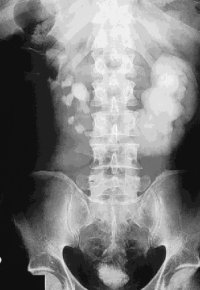

Die postoperative Röntgenkontrolle zeigt die Normalisierung der linksseitigen Abflussverhältnisse (Abbildung 10).